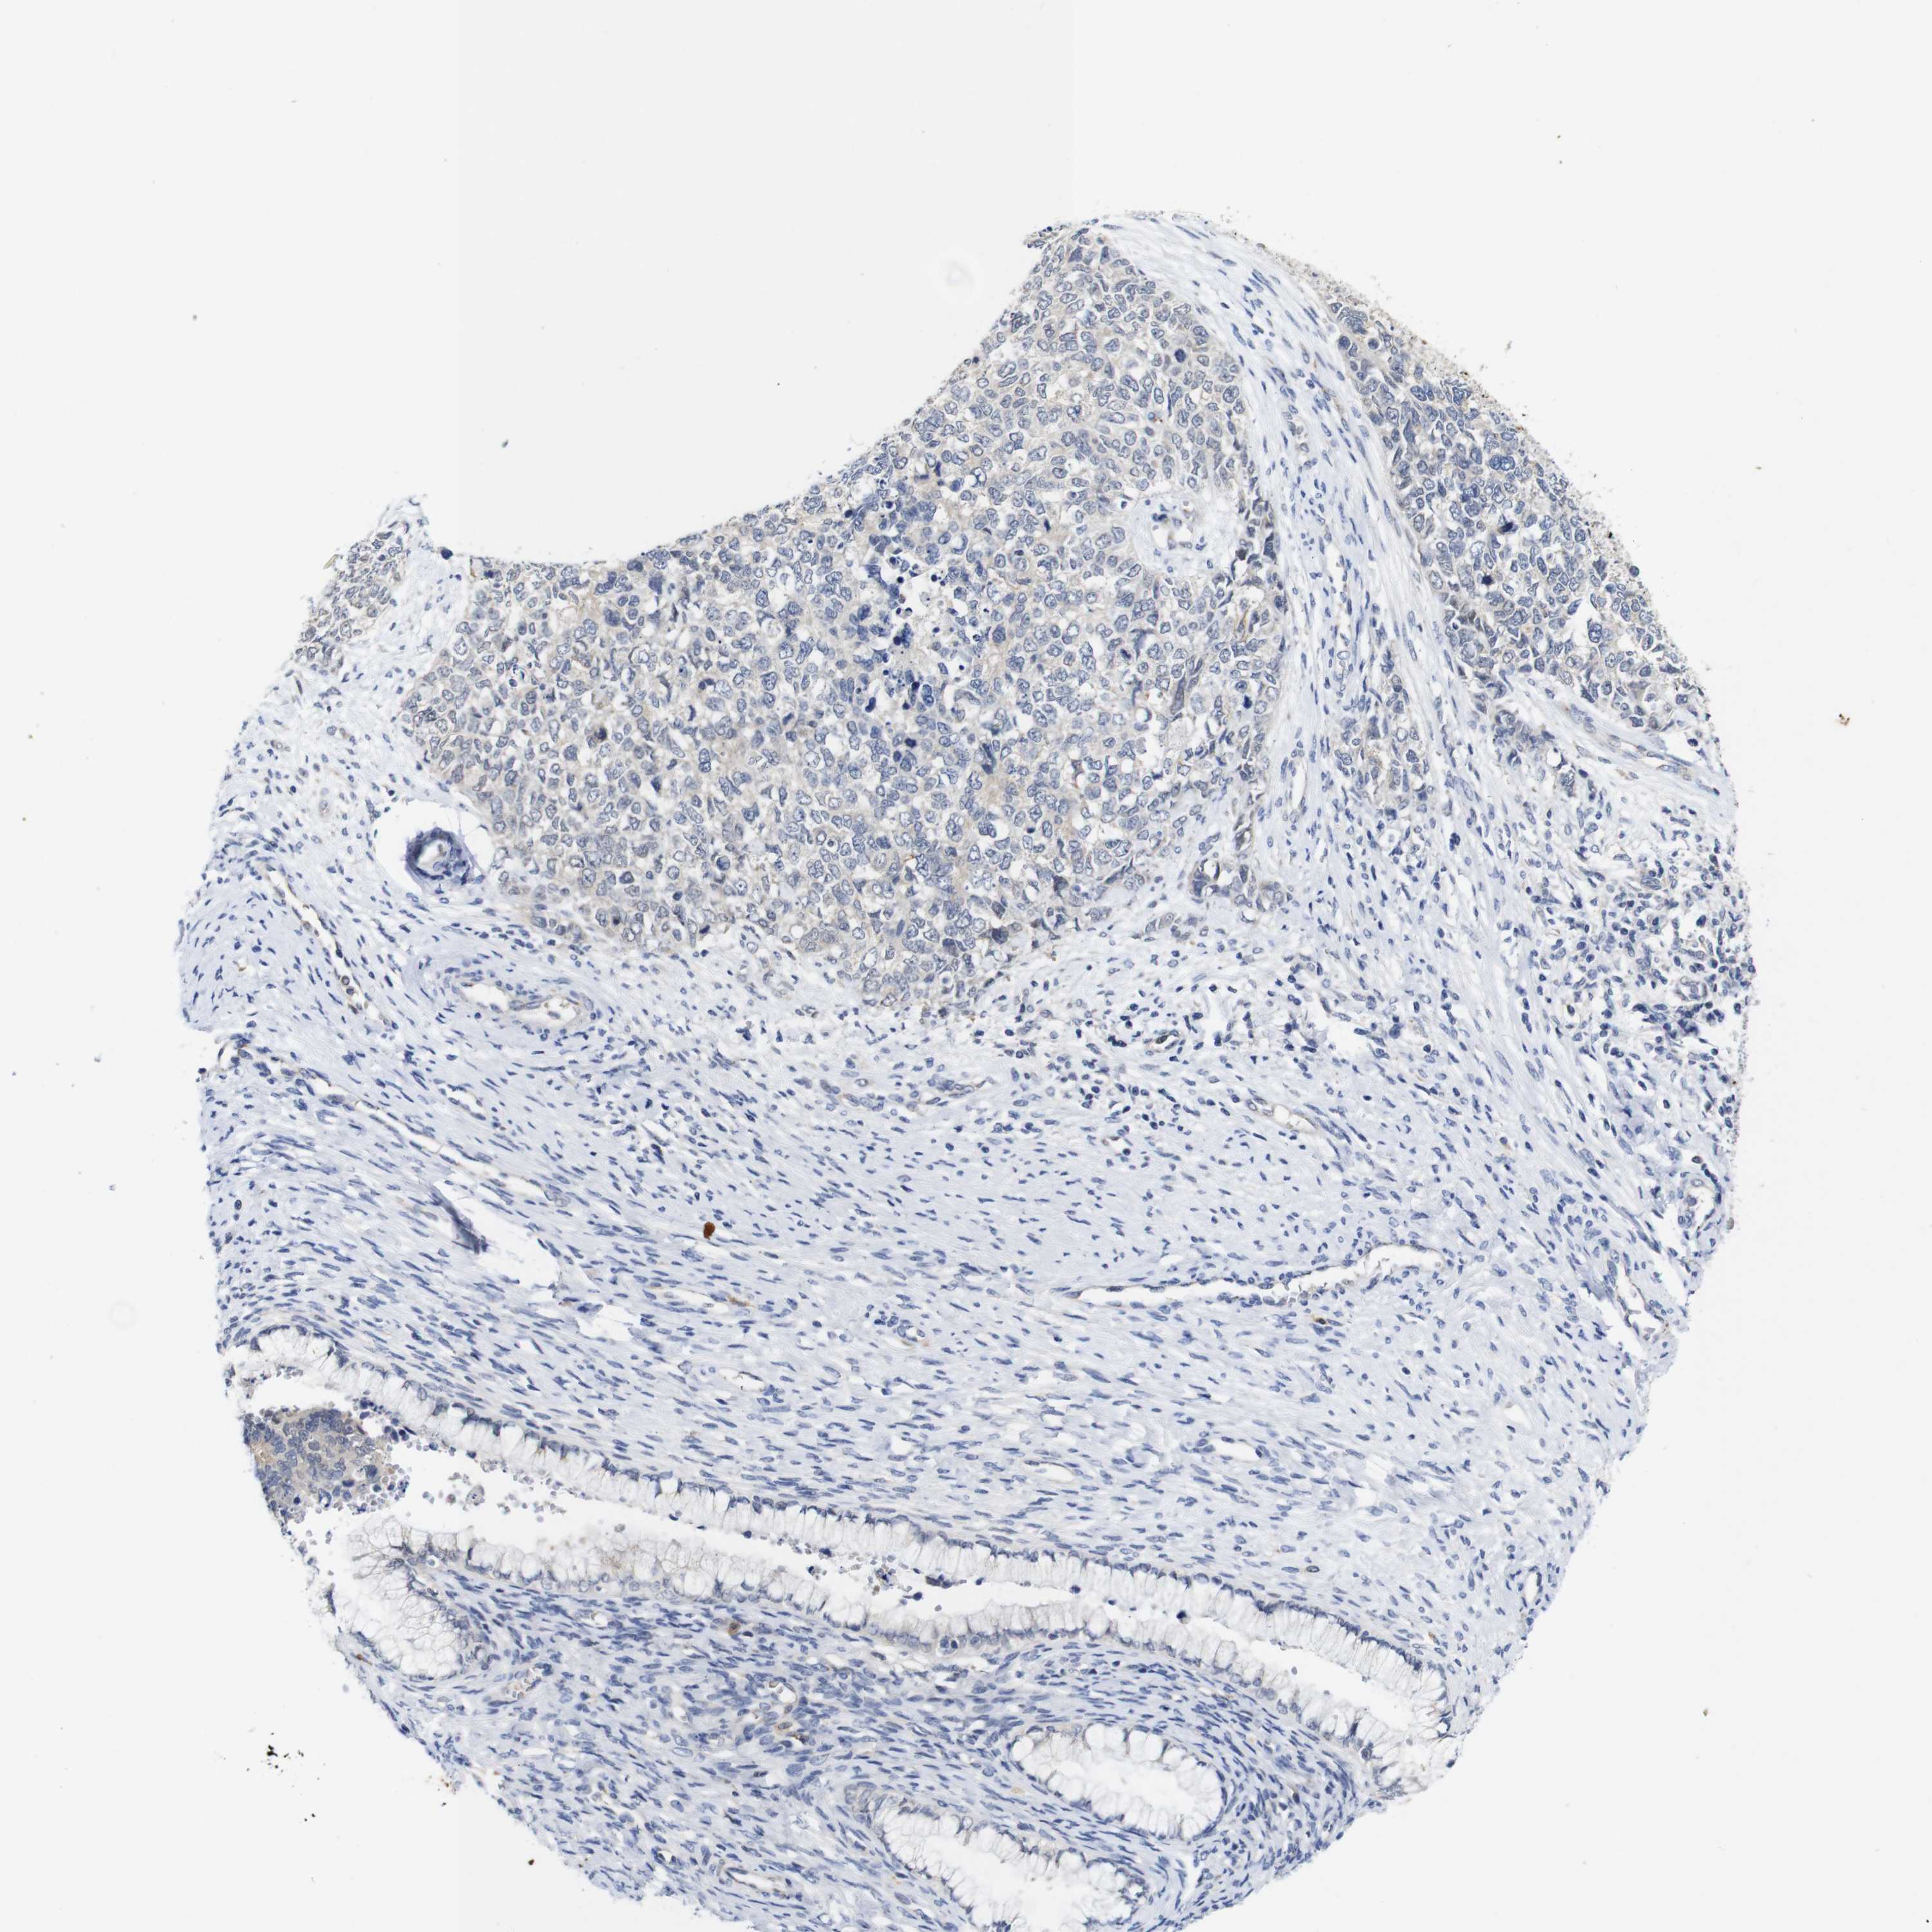

CERVICAL CANCER - Protein expressioni

A mouse-over function shows sample information and annotation data. Click on an image to view it in a full screen mode. Samples can be filtered based on level of antibody staining by selecting one or several of the following categories: high, medium, low and not detected. The assay and annotation is described here.

Note that samples used for immunohistochemistry by the Human Protein Atlas do not correspond to samples in the TCGA dataset.

Antibody stainingi

Antibody staining in the annotated cell types in the current human tissue is reported as not detected, low, medium, or high, based on conventional immunohistochemistry profiling in selected tissues. This score is based on the combination of the staining intensity and fraction of stained cells.

Each image is clickable and will lead to virtual microscopy that enables deeper exploration of all samples and also displays staining intensity scores, fraction scores and subcellular localization as well as patient and tissue information for each sample.

Antibody HPA067869

Antibody CAB009499

Staining

High

Medium

Low

Not detected

Intensity

Strong

Moderate

Weak

Negative

Quantity

>75%

75%-25%

<25%

None

Location

Nuclear

Cytoplasmic/membranous

Cytoplasmic/membranous,nuclear

Squamous cell carcinoma, NOS

Adenocarcinoma, NOS